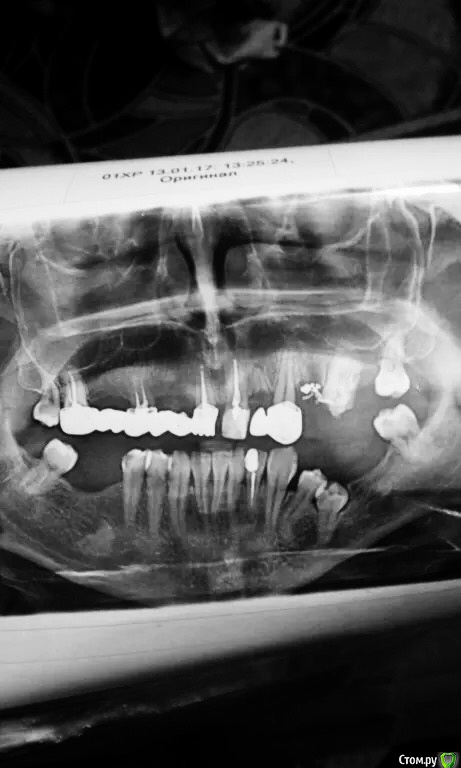

dr.Dre Опубликовано 13 января, 2017 Поделиться Опубликовано 13 января, 2017 Добрый вечер коллеги пациент 30 лет ,лор направил удалить корень 4 убрали была гранулёма,пока не прошло,посмотрите по панорамке данный клинический случай ,какое лечение реально сделать в данной ситуации? Ссылка на комментарий

DmitrySH Опубликовано 14 января, 2017 Поделиться Опубликовано 14 января, 2017 Снимок не особо информативный, но сомнительно что 14 мог быть причиной гайморита. Там до пазухи далеко. Сделайте КТ, посмотрите 17 Ссылка на комментарий

inSight Опубликовано 24 января, 2017 Поделиться Опубликовано 24 января, 2017 По Не увидите пока пазуха гноем не заплывет только КТ или МРТ. КТ редпочтительней так как позволит выявить причинный зуб,если он есьт!Не поймите за грубость - на верняка ошибаюсь, мои познания скудны. Мне стыдно , я даже сижу и извиняюсь. Что такое Воспаление ?! Далее Синусит - классификация по форме. По существу: предложенные методы являются мобильными (быстрыми, общедоступными), КТ конечно более точно и информативно , но учитываете ли факты общедоступности (едет человек с села какого, принесет вам такой снимок) , халатности к снимкам (данная ОПТГшка и коих приносят на глянце, а могут принести и на А4 бумаге распечатанной струйным принтером- к их качеству), цена на КТ? (тысяча рублей и выше, 4часа а то и день траты для снимка, вернется ли он к Вам, когда он приехал от ЛОРа?). КТ спору нет, но в подавляющем большинстве рентген придаточных пазух - достаточно качественного ОПТГ. На данной ОПТГ завал правой стороны головы , стоимость ОПТГшки тоже идет от 800р гадать по ОПТГ которую сделали (сделают не качественно) или отправить на КТ? КТ! А если изначально делать качественно ОПТГ, захватит ли лобные ? Все тлен. Ссылка на комментарий